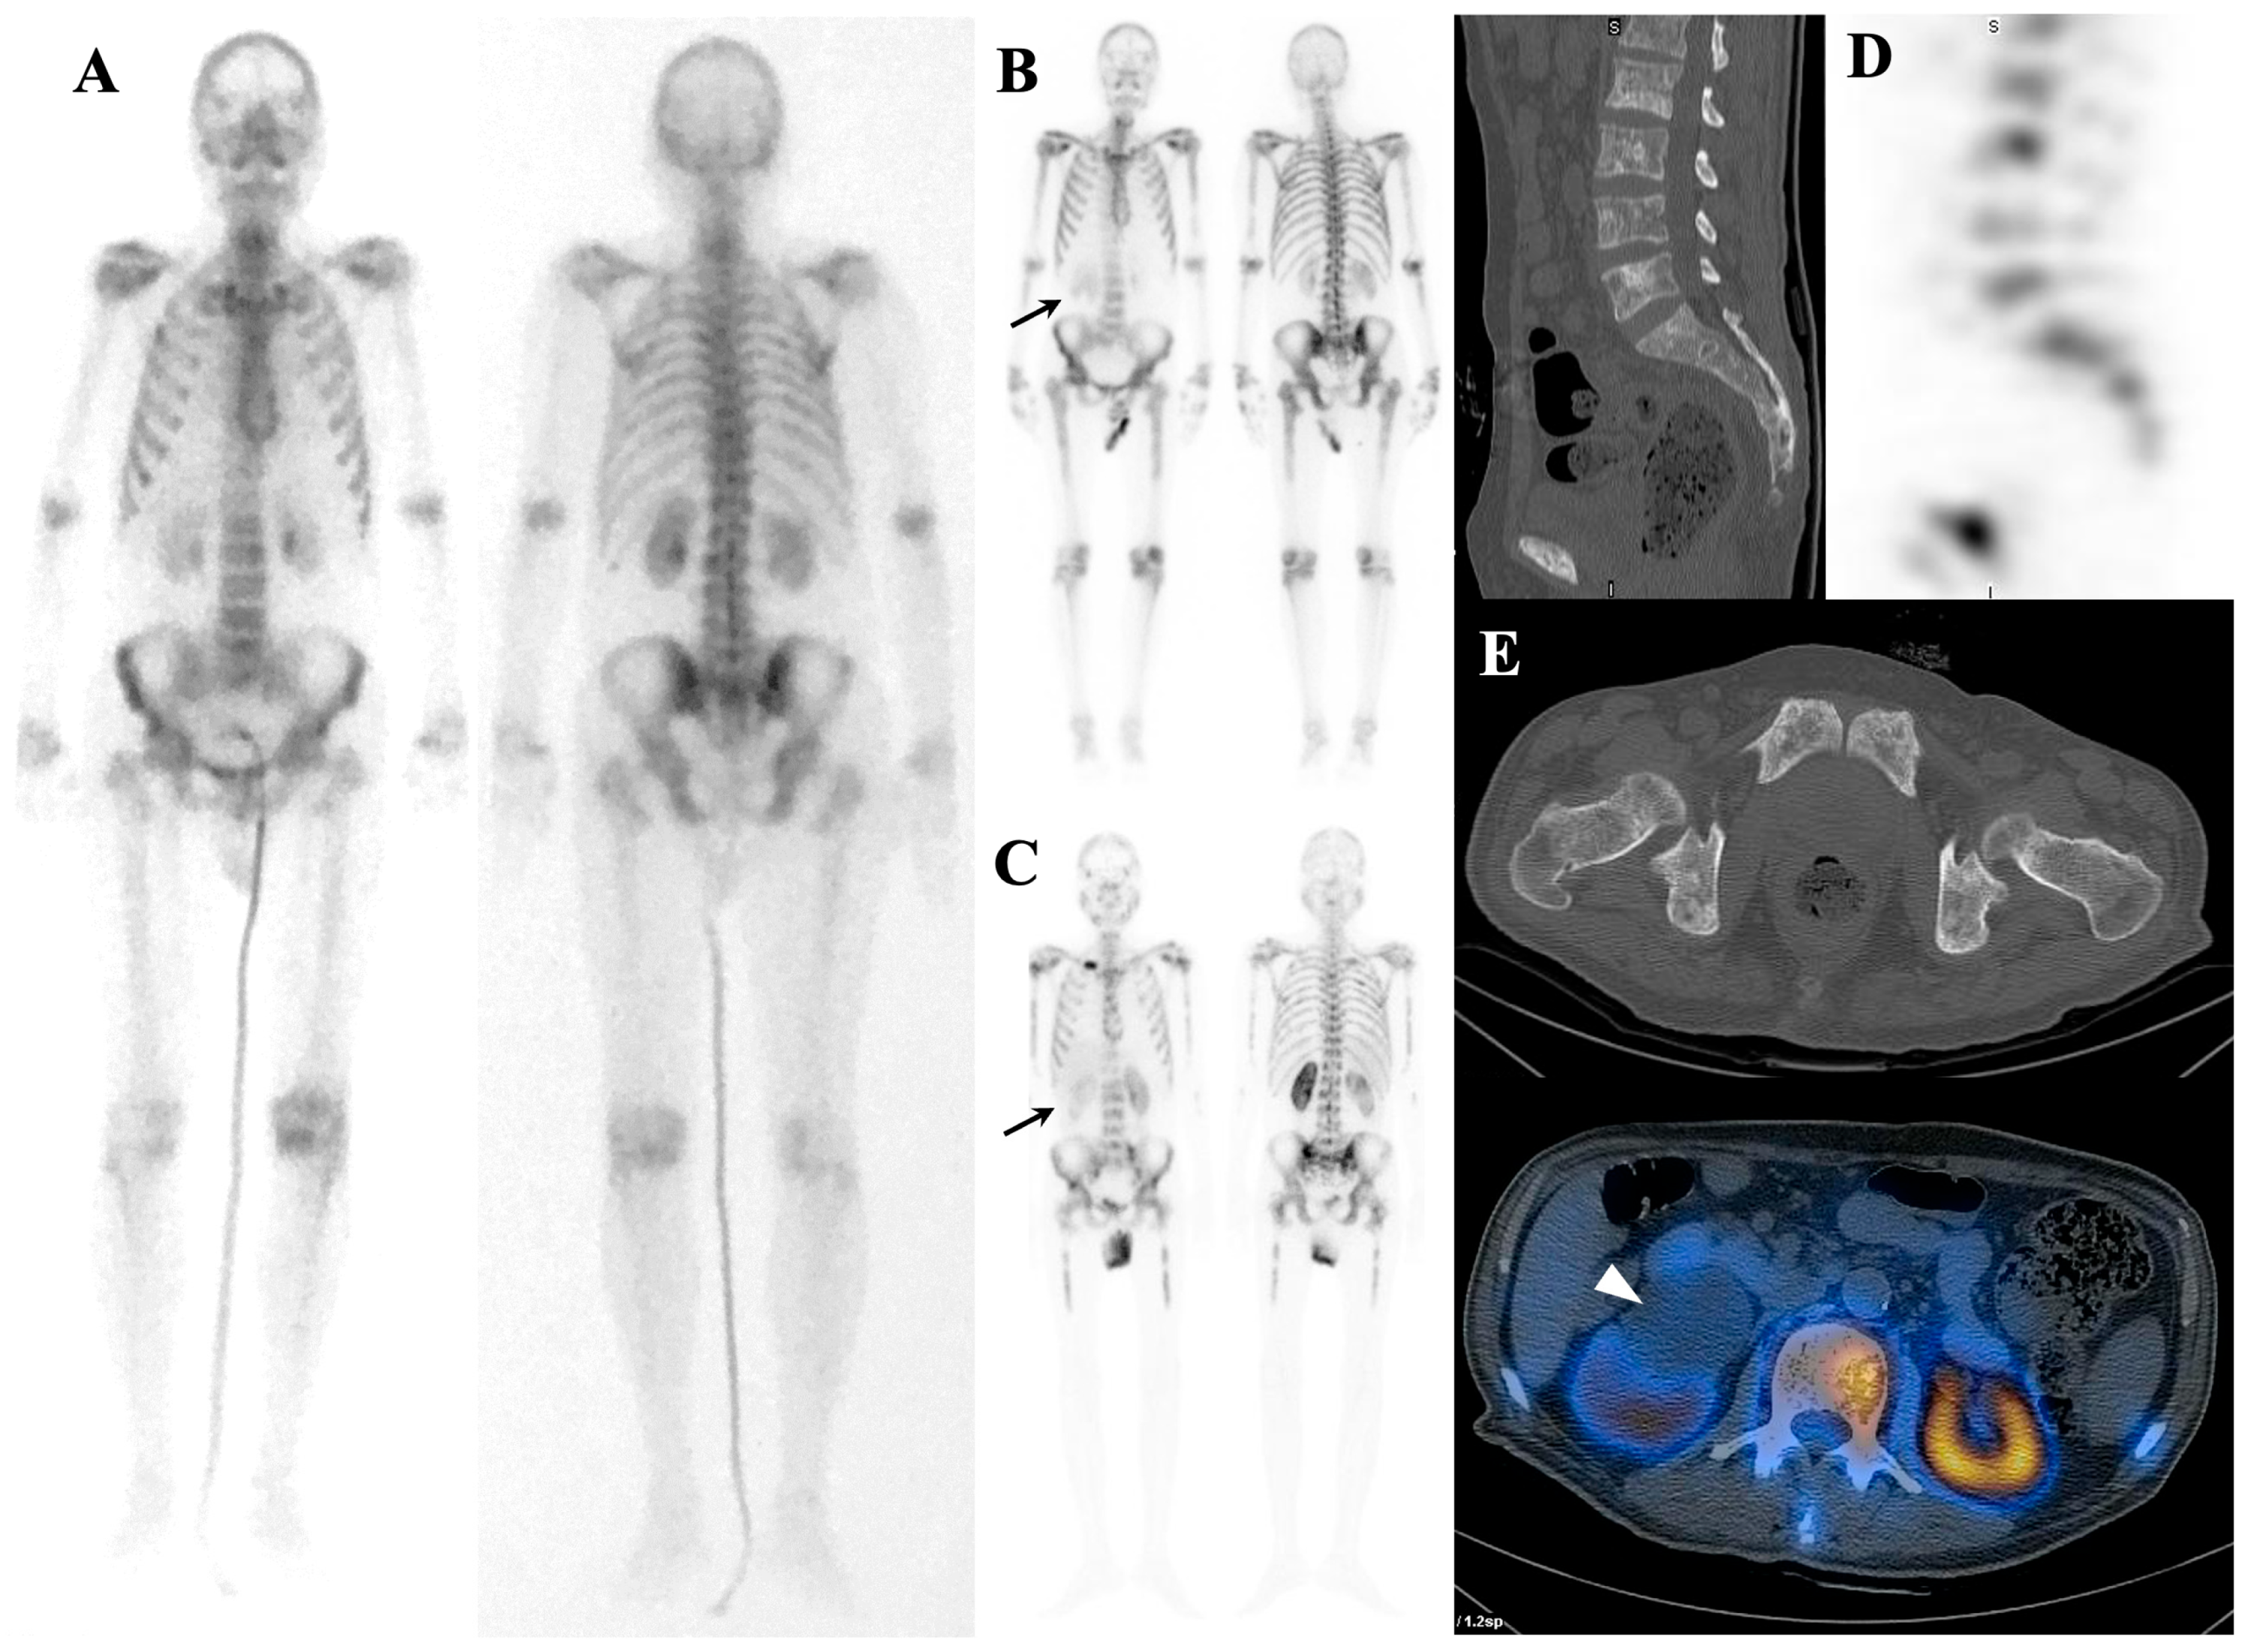

7.1.1. Superscan Pattern in Patients with Prostate Cancer

7.1.2. Dynamic Changes in Prostate Cancer Patients with Superscan

7.2. Metabolic Superscan